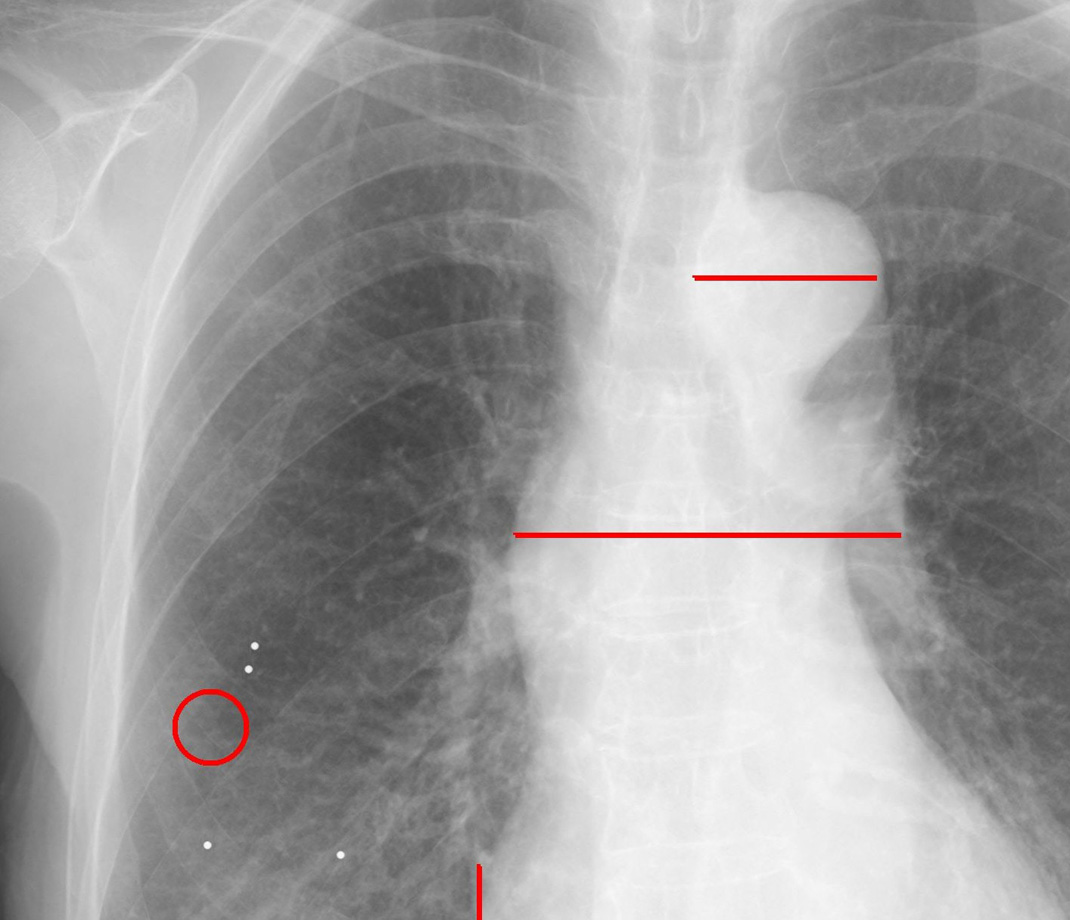

2025年には、県内初となるロボットアーム式リニアック(サイバーナイフ)が当院に導入されました。サイバーナイフは定位放射線治療に特化したリニアックで、腫瘍に集中的に高線量の放射線を照射することが可能であり、外来での肺癌治療が可能です。当科では、病変への正確な照射を目的として、必要に応じて気管支鏡下にゴールドマーカー(直径1.5mm)を留置しています(図4)。

図4 ゴールドマーカー留置後の胸部X線写真: X線写真で見えない小結節(赤い丸)のまわりに、ゴールドマーカー(白い点)が4つ留置されています。